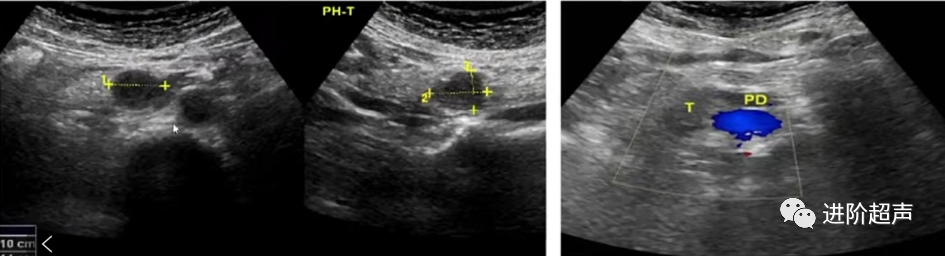

胰体占位

3

胰尾占位

显示胰腺病变的灰阶图像2张 (应为不同角度切面下的图像,建议横切面+纵切面)

病变彩色多普勒血流图像1张,必要时留存频谱多普勒图像1张

如果胰腺发现病变,需增加包含病变的灰阶或CDFI图像至少2张 (应为不同角度切面下的图像,建议横切面 +纵切面)